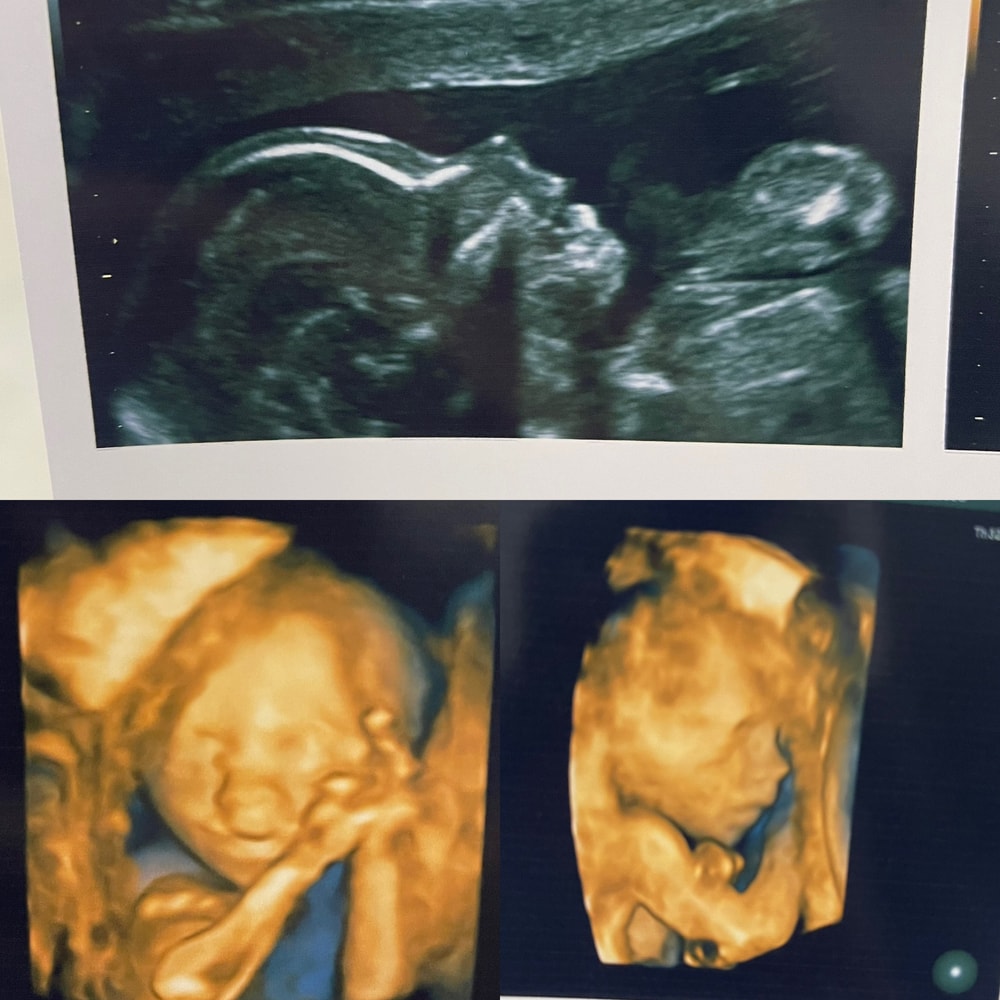

Мама мальчика (3 года), жду девочку, 22 неделя

Как и прогнозировалось - девочка

подскажите, это на каком сроке 3д узи?☺️

Леди мия , это второй скрининг! уже не помню точно, на какой неделе - ну как обычно его делают. Надо поискать) Ну где-то +/- 18, наверное...